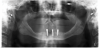

The patient's radiographic assessment, performed immediately following the initial clinical evaluation, included a panoramic radiograph (Figure 4) and bitewing and periapical radiographs of No. 30 (Figure 5). Panoramic findings showed generalized horizontal bone loss confined to the coronal third (15% to 20%), with circumferential bone loss, also referred to as "cupping," around both of the patient's implants, Nos. 30 and 13.

Fig 4. Panoramic radiograph. Both implants (Nos. 13 and 30) demonstrated similar horizontal bone loss confined to the coronal one-third.

Figure 4